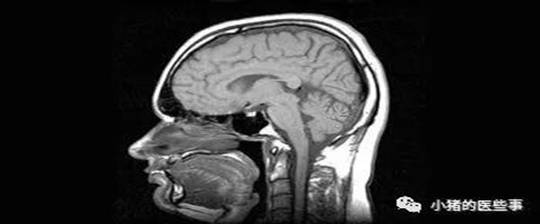

超声、X线、CT、MRI,该如何选择? 无论是看病还是体检,影像学检查总是非常重要的一部分。 超声、X线、CT、MRI,面对多种的检查,有没有产生一些困惑?这个检查是什么?为什么要选这个?为什么做了这个还要做那个?检查是越贵越好吗?...... 如何能根据自身情况,选择最适合的检查项目?专家告诉你每个检查是什么!如何选择检查!如何完成好检查! 一、【检查原理】 超声: [切面里看回声]。超声波穿透人体时产生反射波,收集该反射波信息进行成像,反映该切面内的结构,*用探头获取切面可以对任意切面进行检查*。 X线: [压扁透视看]。就像先将身体压扁,再发射X线穿过人体,由于身体结构的密度厚度对X线阻挡程度不同,最后投射在底片上射线量不同,经过处理形成图像,获得的图像是所有结构的重叠,*按射线发射前至后方向成像*。 CT: [切片透视看]。射线的原理与X线相似,不同的是将身体进行“切片”,显示每一切面里的结构,而不是X线的压缩重叠,*可从正面/侧面/横断进行切片成像*。 MRI(磁共振): [切片看原子运动]。人体内不同结构包含不同量的氢原子,人体进行MRI检查时,相当于体内的氢原子在磁场内进行运动,收集氢原子的运动信息进行切面成像,*正面/侧面/横断进行切片成像*。 二、【如何选择检查】。 不同部位适合的检查不同,下表是各部位与各检查的选择优先度: (没时间可以只看上图) 骨头:首选X线,进一步观察可做CT、MRI可观察里面出血及病变成分情况。 心脏:看心功能及结构首选超声、MRI可观察结构内病变。 腹部及盆部:包括肝胆胰脾肾肠子宫卵巢前列腺等,X线可初步排查胃肠是否穿孔,超声观察除肠管外的实性器官效果好,CT可更进一步明确病灶,MRI更适合对病变成分进行分析鉴别。 胸部:X线是首先要做,进行筛查CT显示效果最好。 皮表包块:指长在表浅部位的小包块,超声是首选,MRI也可对稍大的包块进行分析。 血管:浅表血管(四肢和颈部)超声好,深部血管(大脑及心、胸、腹部)CT好。 浅表器官:包括乳腺和甲状腺腮腺等等,超声是首选,MRI也可分析鉴别,其中X线中的钼靶是乳腺检查的重要部分。 脑及神经:MRI是首选,超声可初步检查表浅的神经。 以下是你们关注的费用和辐射等问题: 三、【如何做好检查】 是否禁食及需要大量喝水?与检查方式无关,与检查部位有关,腹部检查需要禁食6小时以上;腹部检查可在检查前大量饮水;泌尿系检查需要多喝水憋尿。 保持静止,进行检查时不要说话不要动,身体尽可能保持静止(就像你拍照时,动就会模糊~这个道理)。 动作配合。为了更好显示结构,做不同部位检查时,常要配合工作人员做特定动作,超声腹部检查常需要憋气鼓起肚子;颈椎X线检查常需要头后仰前伸张口。4大检查的特点都不一样,医生会根据实际情况进行选择。相信医生,好好配合,你会获得最好的效果! |